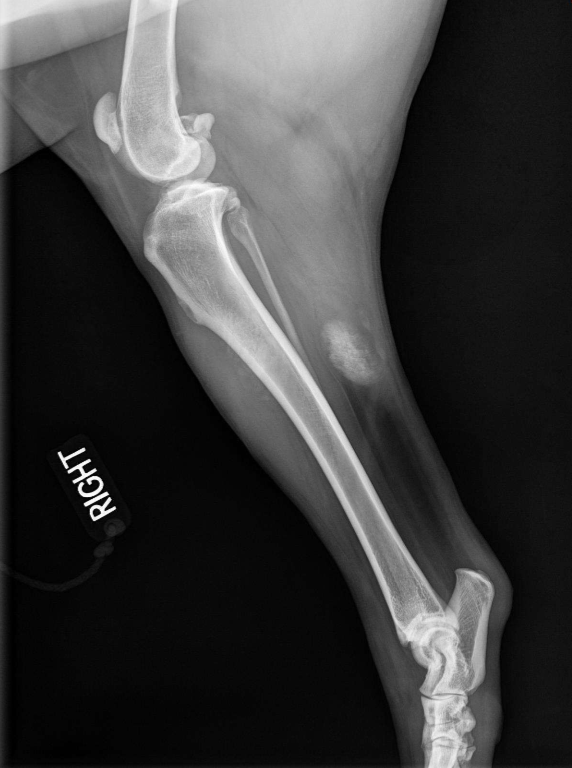

Permeative lysis

Permeative lysis and a fracture